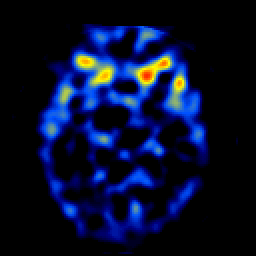

SPECT TL Study #4 -- Slice #23